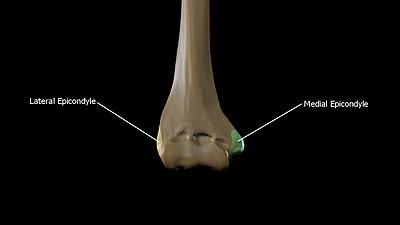

Epicondyles

The epicondyles are continuous above with the supracondylar ridges.

• The lateral epicondyle is a small, tuberculated eminence, curved a little forward, and giving attachment to the radial collateral ligament of the elbow-joint, and to a tendon common to the origin of the Supinator and some of the Extensor muscles.

• The medial epicondyle, larger and more prominent than the lateral, is directed a little backward; it gives attachment to the ulnar collateral ligament of the elbow-joint, to the Pronator teres, and to a common tendon of origin of some of the Flexor muscles of the forearm; the ulnar nerve runs in a groove on the back of this epicondyle.

Medial and Lateral epicondyles of the Humerus